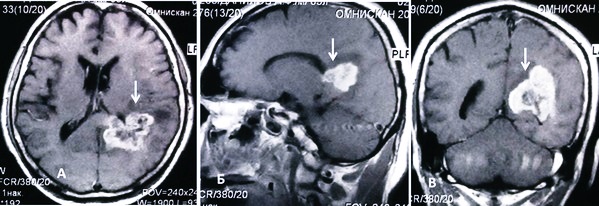

Для точного определения наличия глиомы специалисты рекомендуют проводить магнитно-резонансную томографию (МРТ), которая позволяет визуализировать опухоль и оценить ее характеристики. В некоторых случаях может потребоваться биопсия для подтверждения диагноза. Врачи подчеркивают важность раннего обращения к специалистам при появлении настораживающих симптомов, так как это значительно увеличивает шансы на успешное лечение и улучшение качества жизни пациента.

Важно дифференцировать заболевание от абсцесса мозга, гематомы, эпилепсии, инсульта, других опухолей ЦНС. Сейчас чаще всего назначается МРТ. Это самый современный метод для диагностики. Если ее нельзя провести, могут назначить компьютерную томографию, МСКТ, сцинтиграфию, ангиографию (с применением контраста).

Томография позитронно-эмиссионная (ПЭТ) помогает определить характеристики метаболизма. Так врач узнает, быстро ли растет опухоль, агрессивна ли она. Иногда для диагностики назначают люмбальную пункцию. При этом берут на анализ цереброспинальную жидкость. Если есть глиома, в ней будут обнаружены раковые клетки. Это довольно опасный метод, потому он используется лишь при необходимости.

Все эти методики являются неинвазивными. Они помогают установить, есть ли злокачественная опухоль, как она развивается, как воздействует на метаболизм. Но для постановки точного диагноза нужно исследовать ткани ракового узла. Такой анализ поможет установить вид глиомы, степень злокачественности. Для этого проводится операция – стереотаксическая биопсия.